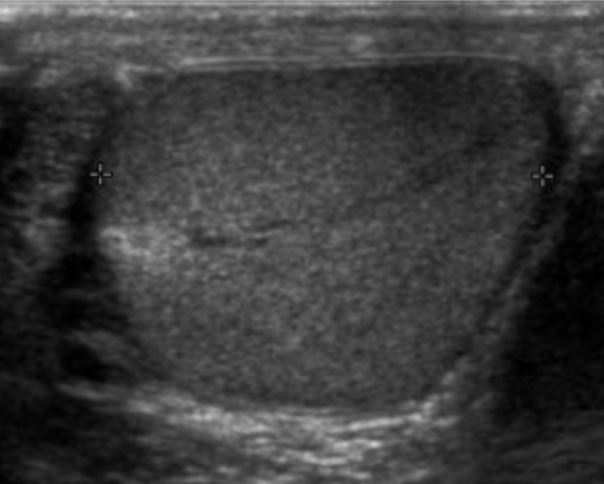

Sentinel Node Biopsy In Clinical Stage I Testicular Cancer | Cancer Network

testis sonography testicular mediastinum hyperechoic biopsy homogeneous sentinel cancernetwork